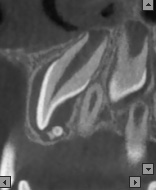

Recently, there has been improvement in X-ray diagnostic imaging methods, especially with regard to CBCT, which certainly facilitates arriving at diagnosis as early as at the stage of radiological examination. Jayam et al. describe a case of an 11-year-old girl with a radiological picture (panoramic radiography, a tooth X-ray and a maxillary occlusal radiograph) description of impacted tooth 11 with an additional cusp and an extensive dentigerous cyst.2 In the course of marsupialization, the dentigerous cyst was found to have no contact with tooth 11, while it contacted the adjacent additional cusp. On histopathological examination, OCp was diagnosed with a cyst. According to some authors, X-ray images – panoramic radiographs and targeted dental X-rays – may not accurately reveal the pattern of the lesion, which is why cross-sectional CBCT is recommended in the case of doubts or for more accurately determining the location.2 In the case of 2 of our patients, it was not until a CBCT was performed that the adequate diagnosis was reached, and it was later confirmed during the procedure and histopathological examination. The first patient was a 9-year-old girl referred to an orthodontist in our clinic due to impacted tooth 21 for the exposure of the tooth and the application of a bracket to the crown of tooth 21. The patient had with her a current panoramic radiograph with visible impacted tooth 21, showing a small non-distinctive radiopacity in the tooth crown, which could be consistent with an additional cusp. An X-ray of tooth 21 was performed at our clinic, revealing a non-distinctive area of radiopacity next to the crown of tooth 21 (Figure 7). The patient was referred for cross-sectional CBCT. After verification, OCp was diagnosed and removed with its capsule, and an orthodontic bracket was attached to tooth 21 in local anesthesia (Figure 8). Histopathological examination confirmed the preliminary diagnosis of OCp. The other patient was a 5-year-old girl who was admitted to our clinic with a missing deciduous tooth 65. The patient had a current panoramic radiograph with her, revealing an impacted tooth (most probably tooth 65) with a non-distinctive area of radiopacity (Figure 9). Cross-sectional CBCT was recommended. In the X-ray image, the preliminary diagnosis suggested OCp with the impacted deciduous tooth 65 above it and the tooth bud of permanent tooth 25 on the palatal side (Figure 10). The procedure involved the resection of the impacted deciduous tooth 65 and the enucleation of the odontoma with its capsule; the tooth bud of tooth 25 was left. Due to the child’s age and her poor cooperation, the procedure was carried out in general anesthesia. Histopathological findings revealed OCp.